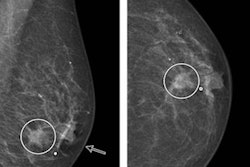

New research suggests removing additional tissue around the tumor cavity for patients with ductal carcinoma in situ (DCIS) can reduce the rate of positive margins, according to a study published in the Journal of the American College of Surgeons.

DCIS accounts for approximately one of every four new breast cancer cases in the U.S, according to the American Cancer Society. If left untreated, DCIS has the potential to evolve into invasive cancer, so many patients choose to have breast-conserving surgery or mastectomy after a diagnosis.